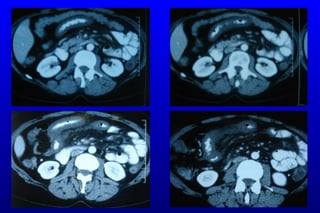

T.A.  55/K Şikayet:  K arın ağrısı Hikaye: 3 gündür devam eden karın  a ğrısı  Ek hastalık:   HT ve atrial fibrilasyon  Kullandığı ilaçlar :  Tarka 180 mg tb 1x1 Coumadin tb 1x1 FM:  TA:130/70 Nb:84,   sol alt kadranda hassasiyet (+) defans (-) rebound(-) barsak sesleri dört kadranda normoaktif  Lab: Lök:15600   Hb:8,6 Hct:29,7 PLT:367000 BK:Normal l a ktat :2,8  Batın BT anjio:  SMA distalinde parsiyel trombüs ve ince barsak tipi hava sıvı seviyeleri

KLİNİK 15/03/2009 :Hasta acil cerrahi kliniğine kabul edildi. Yapılan tetkiklerinde SMA distalinde parsiyel trombüs saptanması üzerine diagnostik laparoskopi yapıldı. Low flow state saptandı. Ameliyat sonrası anjiografi yapılarak tPA  uygulandı. İşlem sonrası yoğun bakıma alınan hastanın sorunu olmadı. 16/03/2009 :Hastaya kontrol anjiografi yapıldı parsiyel trombüs görüntüsü devam ediyor. Hastaya tedavi dozunda DMAH başlandı.

tPA öncesi tPA sonrası

17/03/2009 :Hasta ameliyata alınarak ikincil bakı yapıldı. Laparoskopik eksplorasyonda ince barsaklarda skip tarzında iskemik alanlar saptandı. Üçüncül bakı yapılasına karar verildi.

T.A. 55/KŞikayet: K arın ağrısı Hikaye: 3 gündür devam eden karın a ğrısı Ek hastalık: HT ve atrial fibrilasyon Kullandığı ilaçlar : Tarka 180 mg tb 1x1 Coumadin tb 1x1 FM: TA:130/70 Nb:84, sol alt kadranda hassasiyet (+) defans (-) rebound(-) barsak sesleri dört kadranda normoaktif Lab: Lök:15600 Hb:8,6 Hct:29,7 PLT:367000 BK:Normal l a ktat :2,8 Batın BT anjio: SMA distalinde parsiyel trombüs ve ince barsak tipi hava sıvı seviyeleri

KLİNİK 15/03/2009 :Hastaacil cerrahi kliniğine kabul edildi. Yapılan tetkiklerinde SMA distalinde parsiyel trombüs saptanması üzerine diagnostik laparoskopi yapıldı. Low flow state saptandı. Ameliyat sonrası anjiografi yapılarak tPA uygulandı. İşlem sonrası yoğun bakıma alınan hastanın sorunu olmadı. 16/03/2009 :Hastaya kontrol anjiografi yapıldı parsiyel trombüs görüntüsü devam ediyor. Hastaya tedavi dozunda DMAH başlandı.

17/03/2009 :Hasta ameliyataalınarak ikincil bakı yapıldı. Laparoskopik eksplorasyonda ince barsaklarda skip tarzında iskemik alanlar saptandı. Üçüncül bakı yapılasına karar verildi.

19/03/2009 :Hastaya üçüncülbakı yapıldı. Laparoskopik eksplorasyonda iskeminin kaybolduğu görüldü.Hasta ekstübe edildi. Takiplerinde sorunu olmadı.